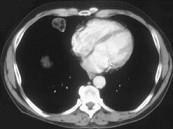

男,57岁,体检时发现肺部占位,CT检查如图,请选出最可能的诊断 ( )A.肺错构瘤B.周围型肺癌C.肺结核D.肺转移瘤E.肺曲菌病

问题 男,57岁,体检时发现肺部占位,CT检查如图,请选出最可能的诊断 ( )

选项 A.肺错构瘤 B.周围型肺癌 C.肺结核 D.肺转移瘤 E.肺曲菌病

答案 A